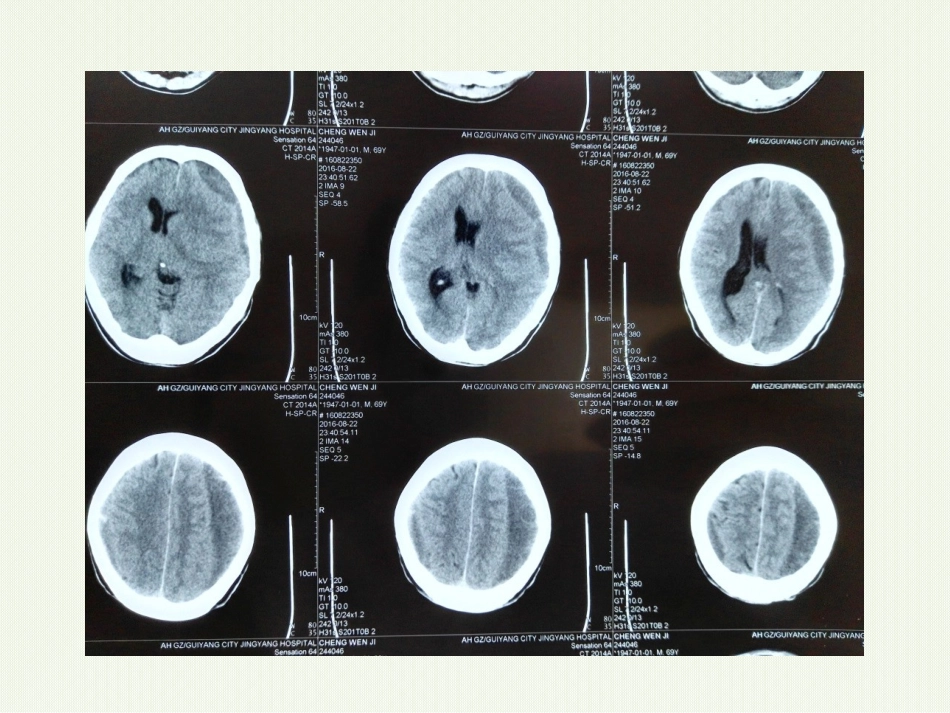

阿托伐他汀钙治疗慢性硬膜下血肿的临床运用michael临床表现主要表现为慢性颅内压增高,神经功能障碍及精神症状,多数病人有头痛、乏力、智力下降、轻度偏瘫及眼底水肿,偶有癫痫及卒中样发作。老年人以痴呆、精神异常和锥体束征阳性为多。小儿常有嗜睡、头颅增大、顶骨膨隆、囟门凸出、抽搐、痉挛及视网膜出血,酷似脑积水。临床分级Ⅰ级:意识清楚、轻微头痛,有轻度神经功能缺失或无;Ⅱ级:定向力差或意识障碍,有轻度偏瘫等神经功能缺失;Ⅲ级:木僵,对痛刺激适当反应,有偏瘫等严重神经功能障碍;Ⅳ级:昏迷,对痛刺激无反应,去大脑强直或去皮质状态。影像学表现CT检查:多表现为颅骨内板下的新月形、半月形或双凸镜形低密度区,体积大、吸收慢或有再出血者,可为高、混杂或低密度影。单侧等密度血肿应注意侧脑室、第三脑室的受压变形与移位,以及同侧脑沟消失等间接征象。增强扫描后可显示血肿包膜。鉴别1.慢性硬膜下积液:多与外伤有关,与慢性硬膜下血肿极为相似。鉴别主要靠CT或MRI.2.大脑半球占位病变:脑肿瘤、脑脓肿等占位性病变。区别主要在于无头部外伤史及较为明显的局限性神经功能缺损体征。确诊需借助影像学资料(CT、MRI)。3.蛛网膜囊肿:病变多位于颅中窝或外侧裂处,一般无严重神经功能障碍症状。CT扫描可见囊肿为均匀一致的低密度影,其形状各异、大小不一。治疗一、手术治疗(首选)手术指征:对慢性硬膜下血肿患者,一旦出现颅内压增高症状,如能耐受手术,均应积极施行手术治疗。术式:顶结节钻孔引流(目前首选、经典)。麻醉方式:局麻。骨瓣开颅血肿清除术:指征:1.血肿内混有血凝块;2.血肿腔内有分隔;3.经钻孔血肿引流不畅或失败者;4.血肿包膜肥厚,或已形成钙化者。手术治疗的局限性:1.易出现血肿复发、脑损伤、张力性气颅、颅内血肿、颅内感染、癫痫、引流管脱落或堵塞;2.医疗费用较高;3.围手术期需要较多家属照顾。在治疗效果基本相似的前提下,能否找到一种更好的治疗方法呢???二、药物治疗阿托伐他汀钙的运用适应症:1.临床分级Ⅰ~Ⅱ级;2.~ⅢⅣ级经手术治疗血肿引流不畅或不理想者;3.高龄患者、严重心肺功能障碍、凝血功能异常,不能耐受手术患者。机制:阿托伐他汀属于他汀类药物,能促进血管生成和增加内皮祖细胞的流通,这对于新的静脉回流生成具有重要作用;同时能抑制炎症反应,降低促炎因子的生成;因此,可能通过提升血脑屏障的交换,促进血液流动,减少炎症反应,达到对慢性硬膜下血肿的治疗作用。或阿托伐他汀能促进血管修复、生成与血液重吸收,逐渐改善血肿情况,可以从本质上对血肿进行根治,有利于彻底消除血肿。优点:1.操作简单易行,口服药物不需要专业的医务人员;2.医疗费用明显降低;3.无痛苦,无手术风险,家属及患者容易接受;4.无颅内感染、出血的风险;5.患者无手术后因引流管等原因需要限制体位,不易翻身活动;6.对高龄、全身情况差的患者多了一种治疗方法的选择;7.对于术后残留的血肿,是一种良好的治疗措施。缺点:1.阿托伐他汀可以导致血糖升高,并且会导致新发糖尿病;2.肝肾功能损害、认知功能改变和神经系统损害;3.肌病(横纹肌溶解、肌痛)。注意事项:1.在临床使用过程中,需注意观察病情变化,若出现颅内压增高、脑疝风险时要果断进行手术处理;2.注意监测血糖、肝肾功变化;3.注意患者意识状况及全身情况变化。病例一:患者程某某,男性,69岁,1.左侧额颞顶部慢性硬膜下血肿;2.右侧额顶部亚急性硬膜下血肿。术前术后第1天复查,加用阿托伐他汀钙20mg.po.qd.术后服药7天后复查术后服药2周后复查术后服药3周后复查病例二:患者刘某某,男,61岁,左侧额颞顶部慢性硬膜下血肿。术前术后第1天,加用阿托伐他汀钙20mg.po.qd术后服药1周后复查术后服药2周后复查病例三:患者胡某某,男,41岁,左侧颞部急性硬膜外血肿并左颞顶部硬膜下积液术前术后第1天术后12天复查,加用阿托伐他汀钙20mg.po.qd服药2周后复查,硬膜下积液大部分吸收服药4周后复查,硬膜下积液基本吸收谢谢聆听!